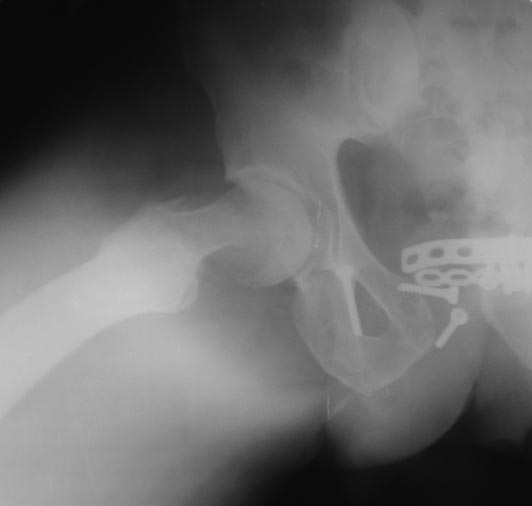

Re: НЕСОСТОЯТЕЛЬНЫЙ ОСТЕОСИНТЕЗ ТАЗА

Второй снимок шейки